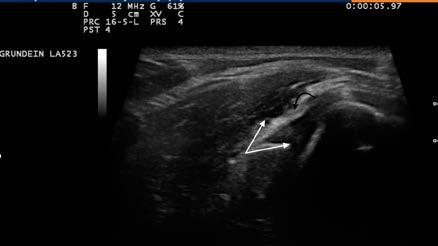

Figura 1. Câine. Radiografie membrul anterior stâng, regiunea antebrațului, incidență latero-laterală. Semne de neomogenitate a matricei osoase (radius), aspect de fum de țigară – panosteită. Radiografie realizată în sistem clasic

în comerț monitoare dedicate pentru imaginile medicale care au o rezoluție crescută. Acest tip de imagini poate fi supus procedurilor de prelucrare post-procesare pentru analiza cantitativă a conținutului informativ, pentru evaluări morfometrice (dimensiuni liniare, unghiuri, suprafață), pentru reconstrucții 3D (fig. 3).

Figura 2. Detaliu al figurii 1